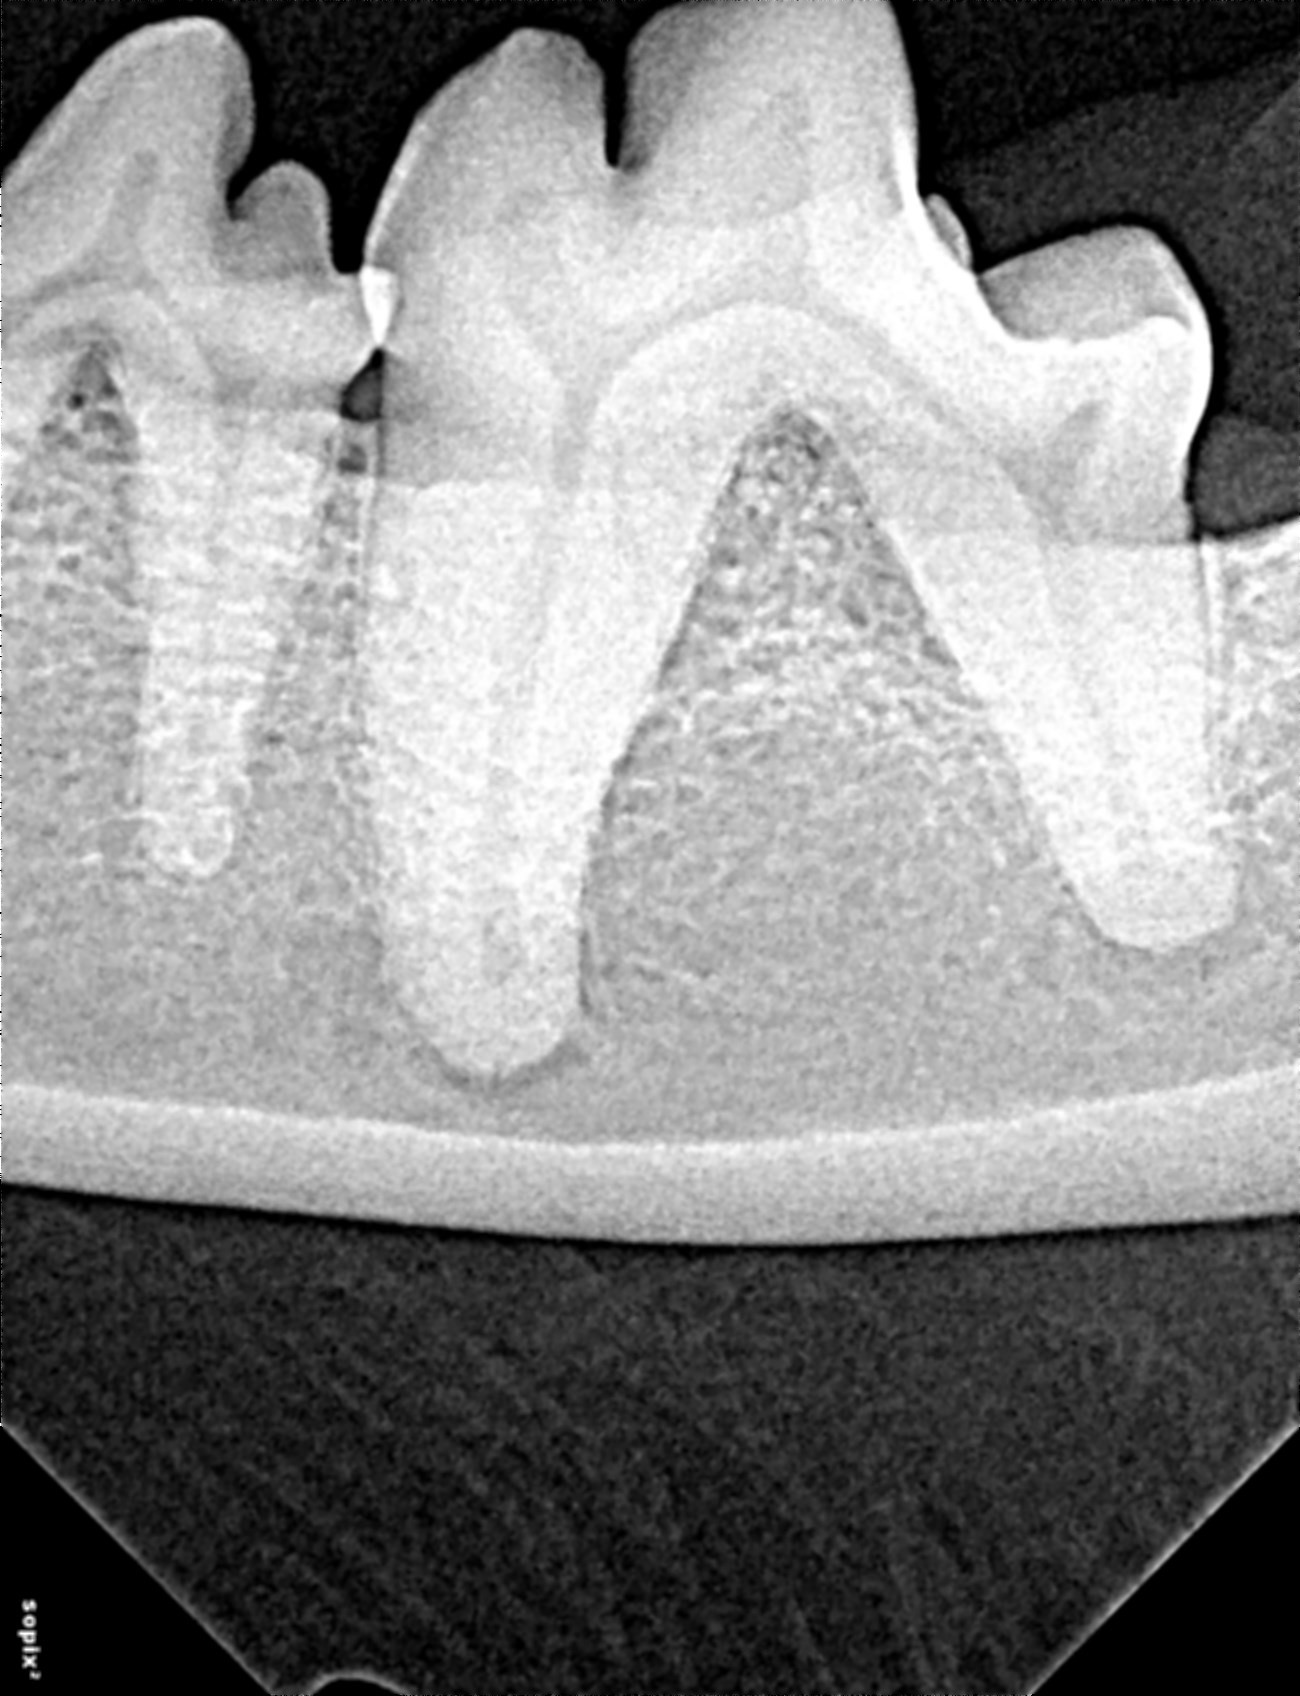

A post-op radiograph showed the furcation successfully filled with the alloplast (Figure 6).

Figure 6. Radiograph 309 after placement of Synergy